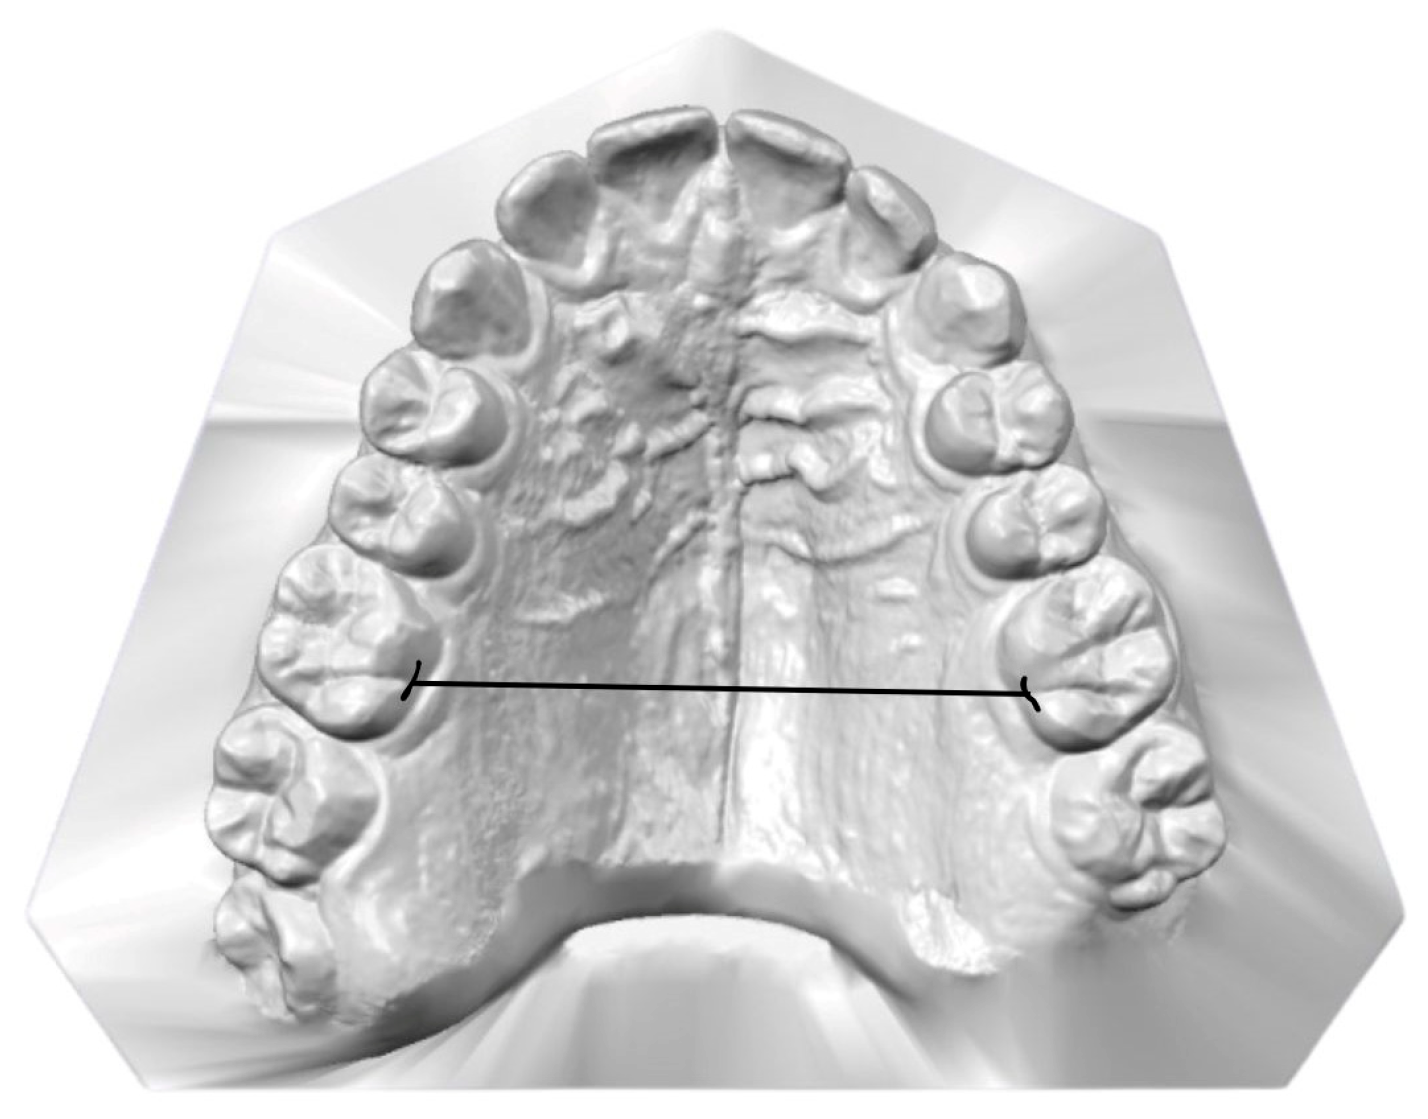

2.3. Data Collection and Measurements